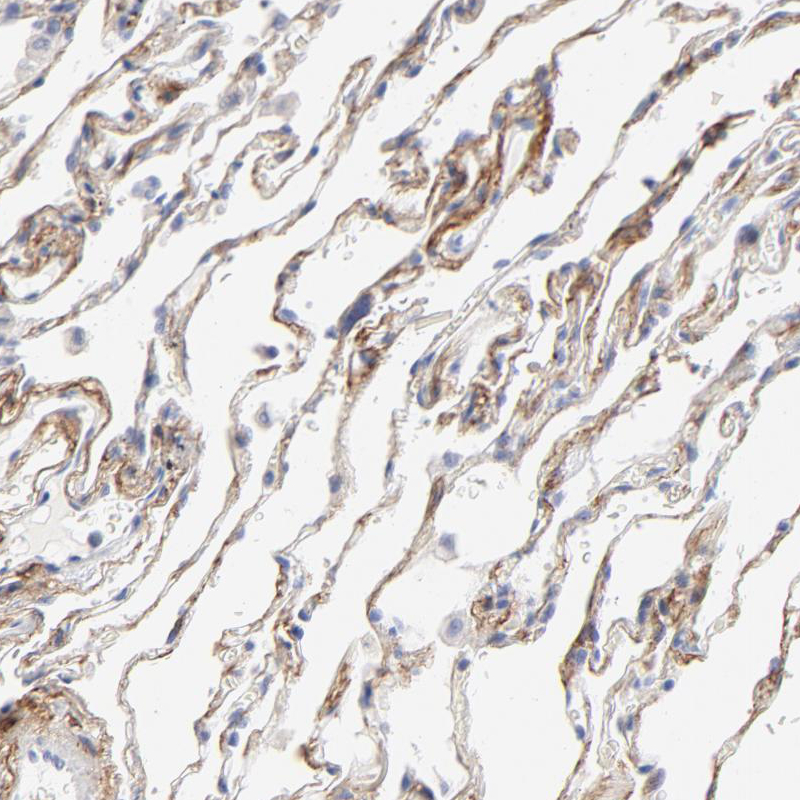

Immunohistochemical staining of human kidney shows strong membranous positivity in cells in glomeruli, while cells in tubules are negative.